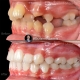

Orthodontic treatment of severe deepbite case with occlusal cant done using MEAW technique. Deebbite with occlusal cant is one of the challenges among Orthodontic treatments and using MEAW technique provide controlling of each single tooth in all 3 dimensions which could shortens the treatment time comparing with other techniques. Another advantage of using MEAW technique in such cases would be the correction of front teeth inclination from the very beginning of treatment and maintaining it till end of the treatment which is a important fact for the long term stability of treatment results.